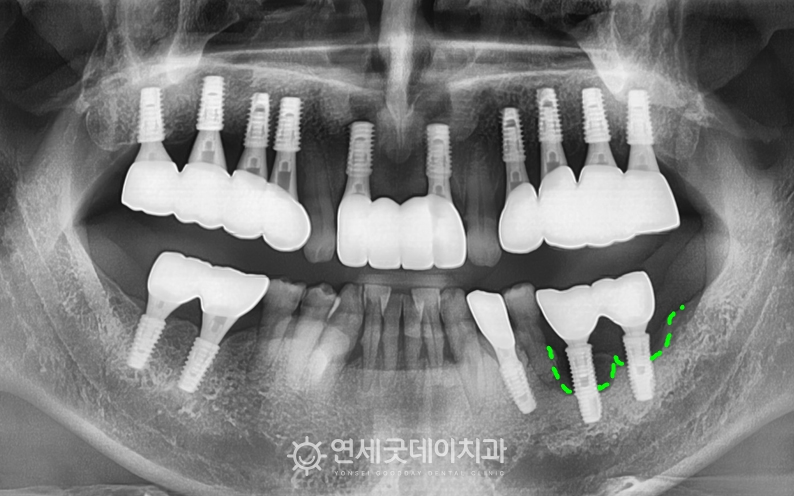

엑스레이를 보면 #35 부위에 치근단 병소가 확인되었고,

치근단염이 관찰되었던 #35 부위를 발치 및 제거 후에는 추후 새로운 임플란트를 안전하게 심고,

환자분은 흡연 조절이 어려우셔서 치료 과정이 쉽진 않았지만

치료전과 후를 보시면 완전히 내려 앉았던 잇몸뼈가